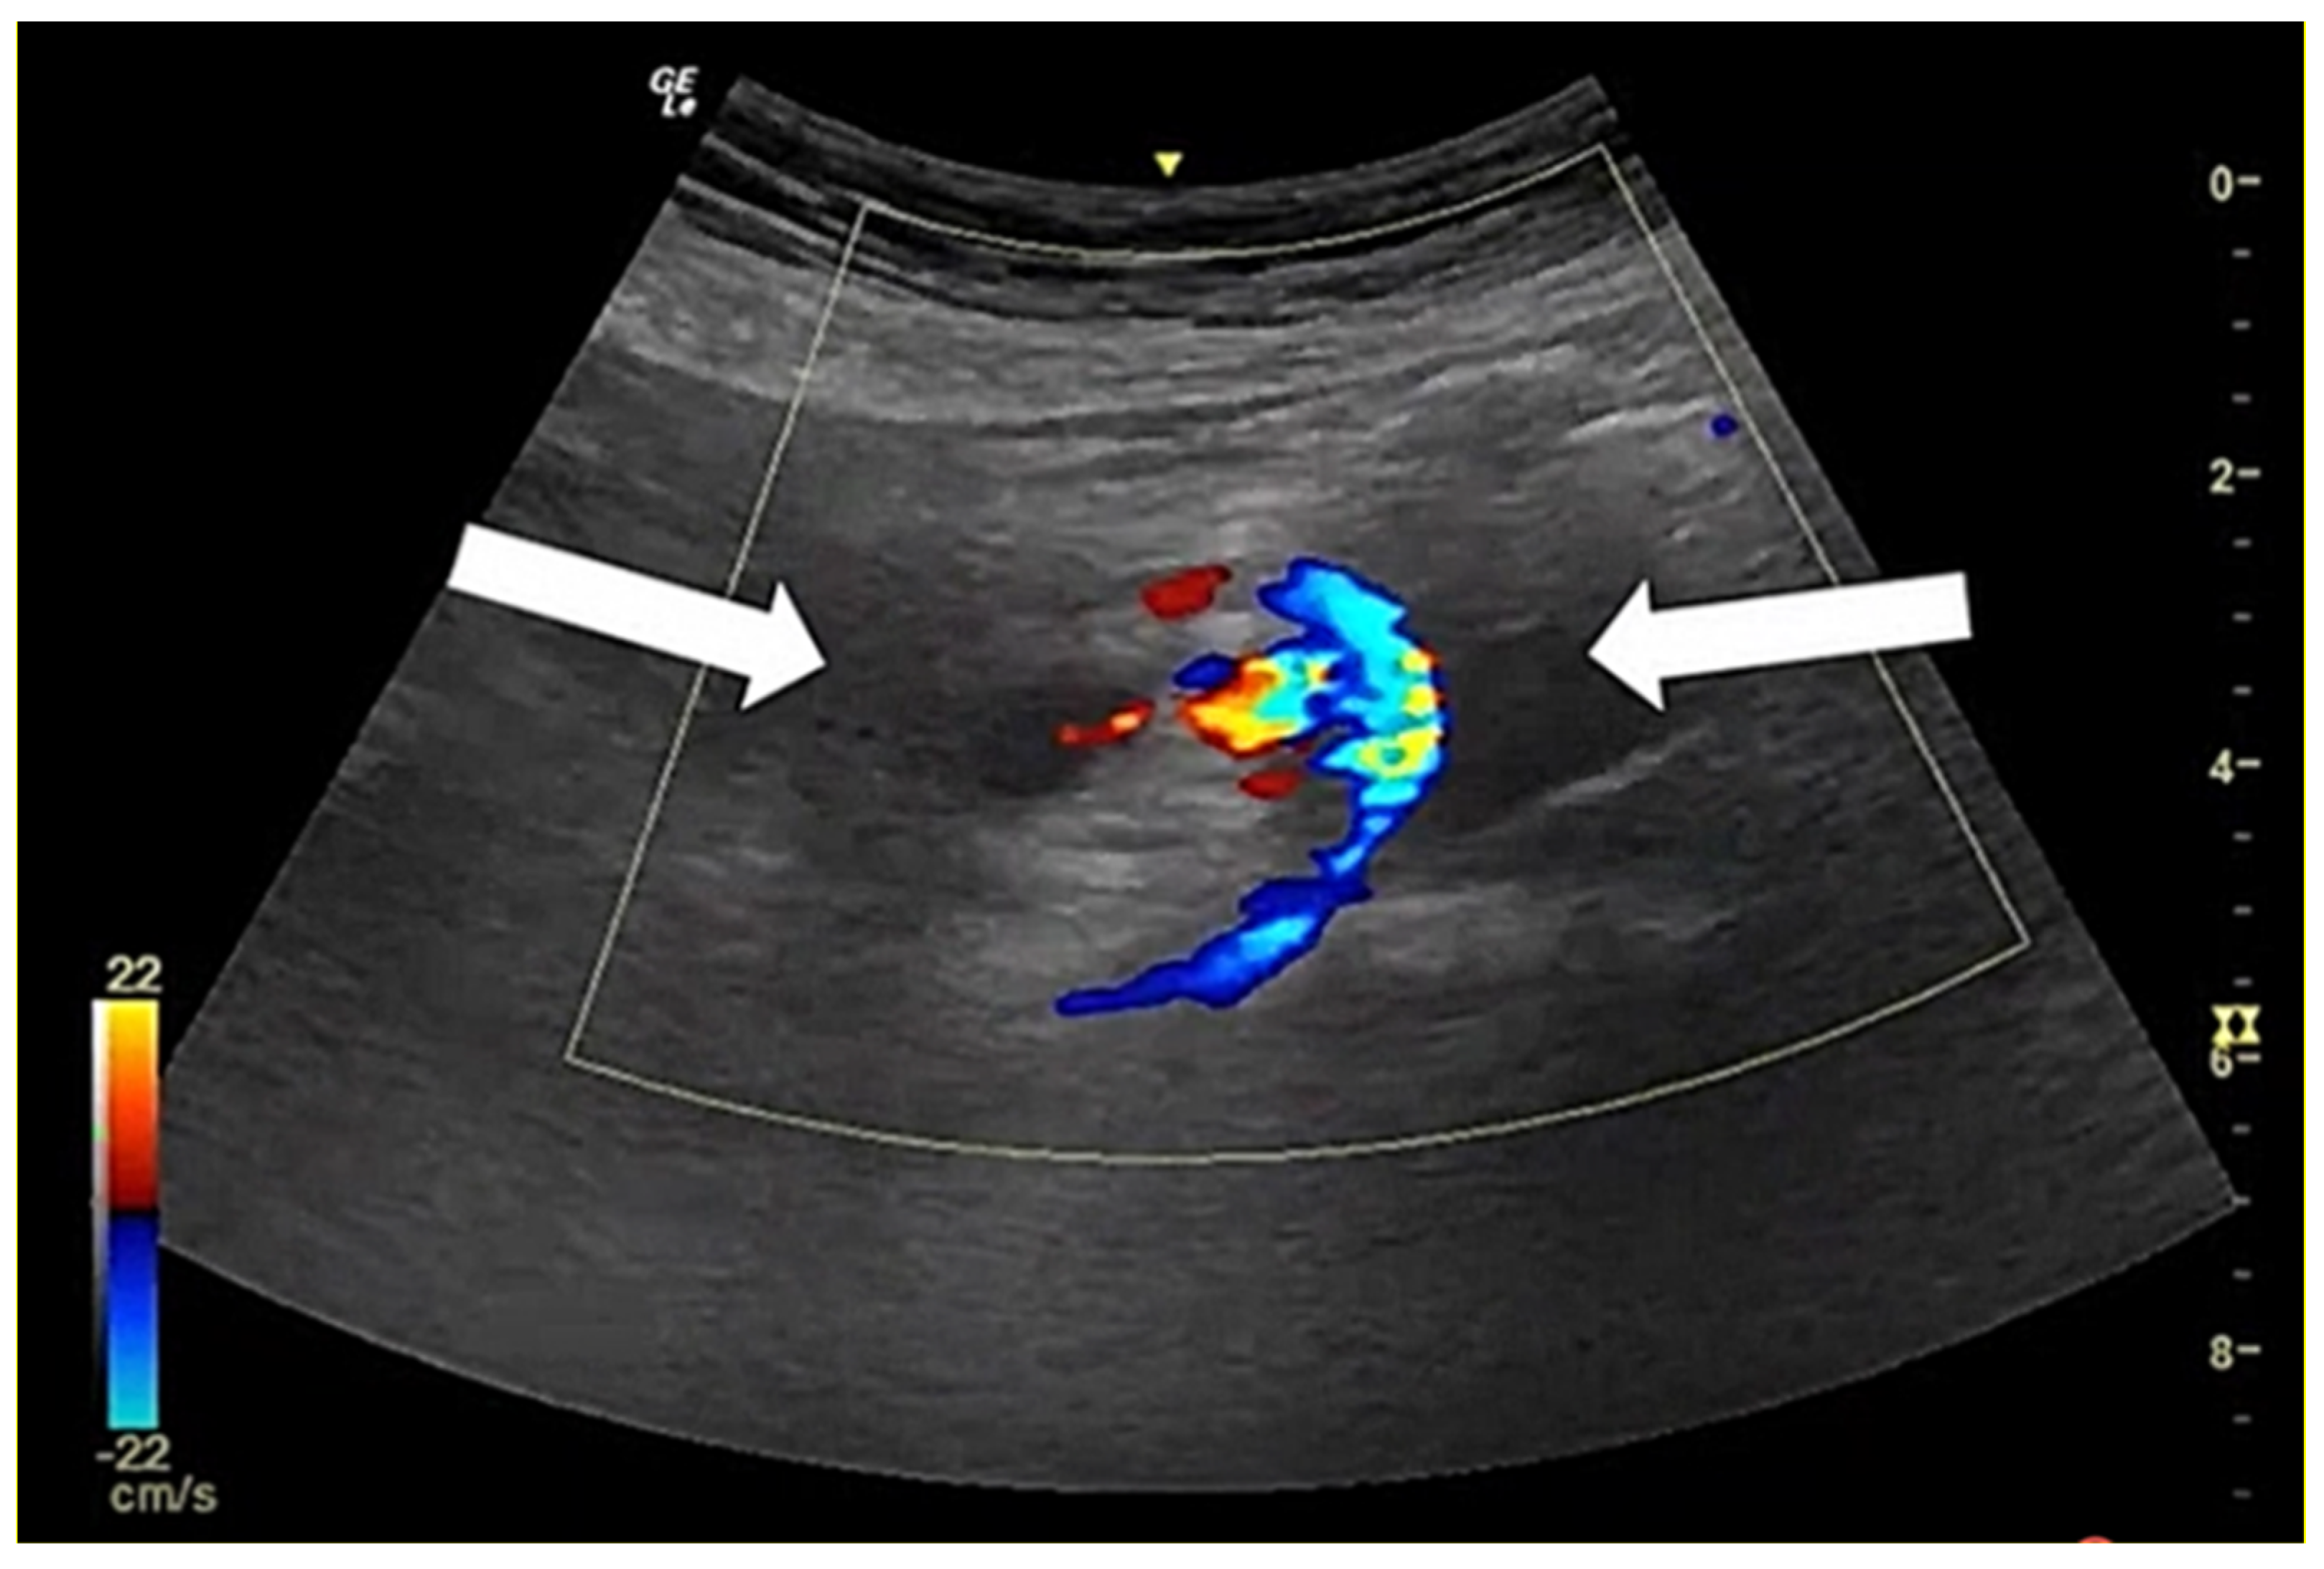

- Enyuma, C.O.A.; Adam, A.; Aigbodion, S.J.; McDowall, J.; Gerber, L.; Buchanan, S.; Laher, A.E. Role of the ultrasonographic ‘whirlpool sign’ in intestinal volvulus: A systematic review and meta-analysis. ANZ J. Surg. 2018, 88, 1108–1116. [Google Scholar] [CrossRef]